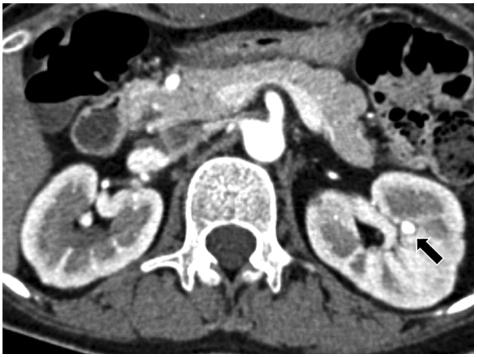

Coronary artery aneurysms are uncommon, are usually associated with atherosclerosis, and rarely involve all three major coronary arteries. The present report describes a rare case of a young female patient presenting with acute myocardial infarction (AMI). Coronary angiography revealed multiple severe aneurysmal and stenotic changes. Based on clinical feature and angiographic findings, it was strongly suspected that the patient had polyarteritis nodosa (PAN) complicated by AMI. The patient was treated with standard cardiac medications and immunosuppressive agents and has remained stable without further complications during a follow-up period of 6 months.

冠状动脉瘤并不常见,通常与动脉粥样硬化有关,很少累及所有三支主要冠状动脉。本报告描述了一例年轻女性患者急性心肌梗死(AMI)的罕见病例。冠状动脉造影显示多处严重的动脉瘤样和狭窄性改变。根据临床特征和血管造影结果,强烈怀疑患者患有结节性多动脉炎(PAN)合并 AMI。患者接受了标准的心脏药物和免疫抑制剂治疗,在 6 个月的随访期间病情稳定,没有进一步的并发症。